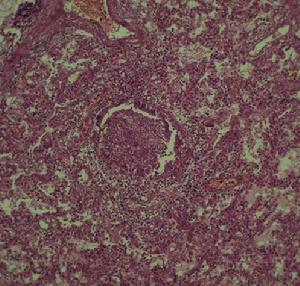

肺蟎病體徵

肺蟎病實驗室檢查:1.一般檢查外周血白細胞正常或輕度增加。嗜酸粒細胞常增高,約占10%~50%。血清IgE明顯增高,可達正常人的5~6倍。IgG和IgA也增高,IgM在疾病早期雖有不同程度增高,但與對照組比較無明顯差異。痰可有較多的嗜酸粒細胞。偶見夏科結晶。留24h痰經5%~7.5%氫氧化鈉消化2~3h,離心塗片鏡檢找到蟎成蟲、幼蟲或卵可確診。

2.免疫學檢查常用的有:(1)皮試:多用蟎變應原點刺試驗(SPT),其總陽性率達80%。(2)間接螢光抗體試驗(IFA):方法簡便,敏感性及特異性均較好,陽性率在90%以上。(3)間接血凝試驗(IHA):陽性率較IFA稍低,約85%,其特異性也較好,診斷肺蟎病時其滴度宜≥1∶16。(4)生物素-親和素酶聯免疫吸附(ABC-ELISA)試驗:方法簡便、快捷、易推廣,其陽性率在80%左右。(5)酶聯免疫吸附試驗(EIISA):採用對蟎蟲病患者血清抗體檢測的一種方法,若以吸光度值OD≥3為陽性,則肺蟎病患者陽性符合率為83%,非肺蟎病呼吸系統疾病患者的陰性符合率為90%,健康人的陰性符合率為95%。由於它具有敏感性高,特異性強的優點,故可用於肺蟎病的診斷和重點人群的流行病學調查。但此等試驗必須與臨床結合,才能正確診斷。其他輔助檢查:X線表現主要徵象有肺門陰影增寬,紋理增粗紊亂,兩肺中下野可見雲霧狀陰影,肺門部及兩肺可有散在、大小不等(2~5mm)的結節狀或斑點狀陰影,此為肺蟎病特徵性的X線表現。有報導肺蟎病X線胸片有此等徵象者達70%~80%。